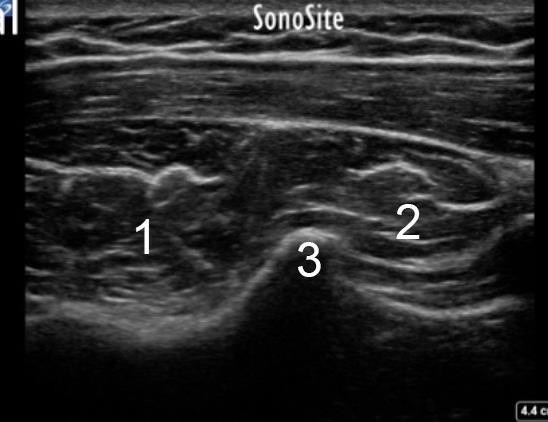

1. Inferior Glenoid Tubercle (where the attachment of the triceps tendon short head is taking place)

2. Triceps Tendon Long Head

3. Bony Ridge on Posterior Scapula that Separates Teres Minor from Infraspinatus